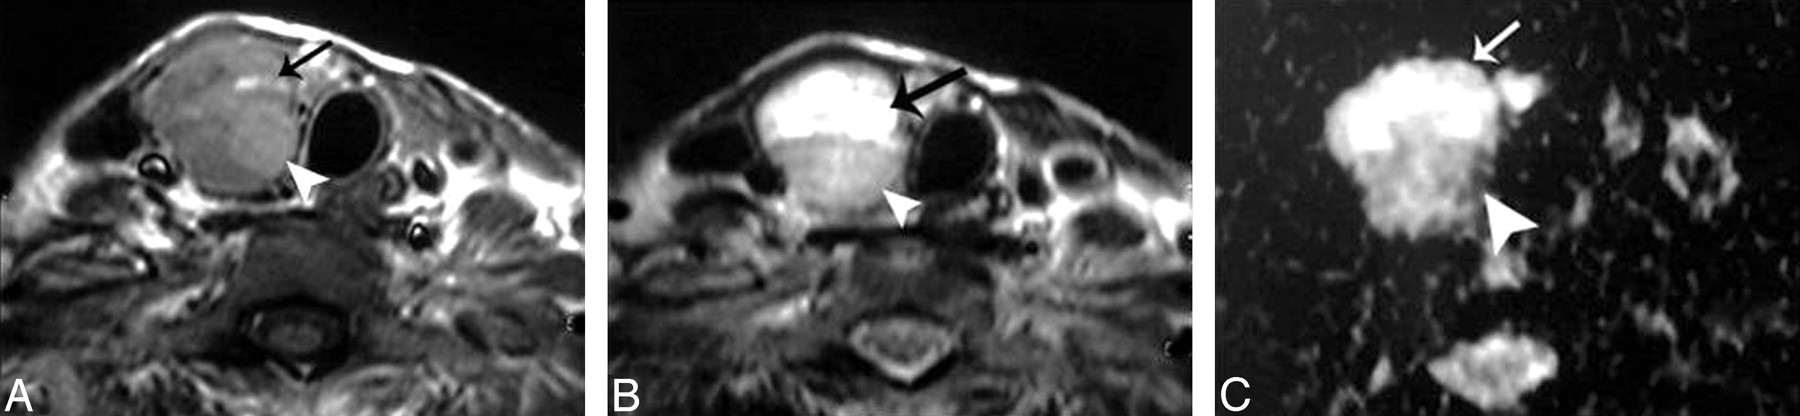

Table 1 illustrates the ADC values of the different histopathologic types of solitary thyroid nodules in this study. The ADC value of the adenomatous nodules ranged from 1.1 to 1.9 × 10−3 mm2/s (Fig 2). Also, the range of the ADC value of the solid part of the follicular adenoma was 1.2–2 × 10−3 mm2/s (Fig 3). The thyroid cysts (Fig 4) revealed the highest mean ADC value (1.9 ± 0.38 × 10−3 mm2/s) apart from 1 patient with hemorrhagic cyst (Fig 5), whose ADC value was 0.5 × 10−3 mm2/s, simulating malignant lesions. The malignant thyroid nodules showed lower ADC values (Figs 6 and 7). The mean ADC value of papillary carcinoma was 0.68 ± 0.23 × 10−3 mm2/s, and that of follicular carcinoma was 0.77 ± 0.17 ×10−3 mm2/s.

Follicular carcinoma of the thyroid. A and B, Axial T1- and T2-weighted MR images, respectively, showing a well-defined more or less oval mainly solid solitary nodule (arrowheads) affecting the right thyroid lobe with contralateral tracheal displacement. C, ADC map image shows a low ADC value (0.92 ± 0.06 × 10−3 mm2/s) of the thyroid nodule (arrowhead).